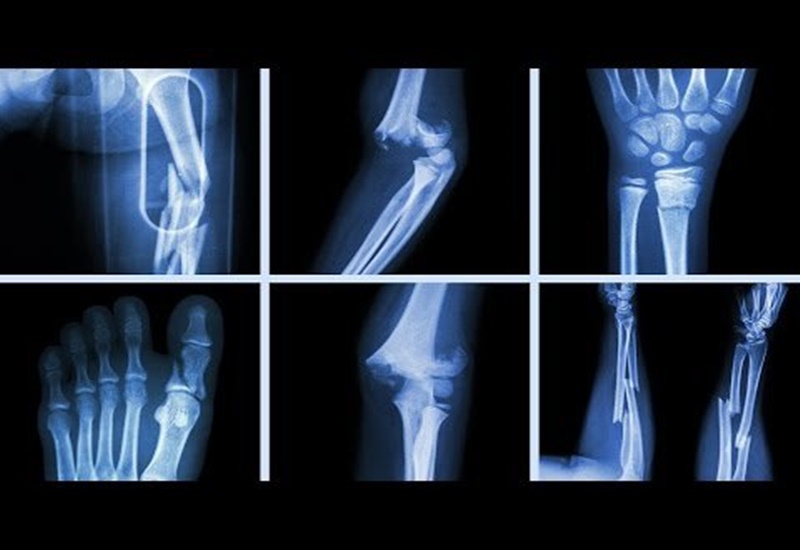

Gãy xương là một tình trạng thường gặp và có thể xảy ra do nhiều nguyên nhân khác nhau, từ tai nạn, thể thao, đến các bệnh lý liên quan đến xương. Tuy nhiên, một vấn đề mà nhiều người gặp phải sau khi gãy xương là quá trình hồi phục lâu dài. Vậy, vì sao gãy xương lâu lành? Bài viết dưới đây sẽ giải đáp câu hỏi này, đồng thời cung cấp những yếu tố ảnh hưởng đến thời gian lành xương và cách thúc đẩy quá trình hồi phục.

Một yếu tố quan trọng ảnh hưởng đến quá trình lành xương là mức độ tổn thương và vị trí gãy. Những trường hợp gãy xương nghiêm trọng như gãy xương mâm chày, cổ xương đùi hay các loại gãy nát cần phải có thời gian phục hồi lâu hơn. Những chấn thương này thường yêu cầu cố định đặc biệt như nẹp, bột hoặc phẫu thuật để giúp xương lành lại.

Ngoài ra, việc gãy ở các vị trí đặc biệt như bàn tay, bàn chân có thể cần thời gian hồi phục ngắn hơn. Ví dụ, gãy xương bàn tay có thể lành trong khoảng từ 4-6 tuần, trong khi gãy xương bàn chân có thể mất từ 3-4 tháng.